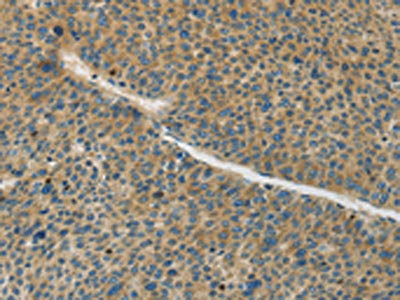

The image on the left is immunohistochemistry of paraffin-embedded Human liver cancer tissue using CSB-PA078531(GJC1 Antibody) at dilution 1/50, on the right is treated with synthetic peptide. (Original magnification: ×200)

The image on the left is immunohistochemistry of paraffin-embedded Human thyroid cancer tissue using CSB-PA078531(GJC1 Antibody) at dilution 1/50, on the right is treated with synthetic peptide. (Original magnification: ×200)